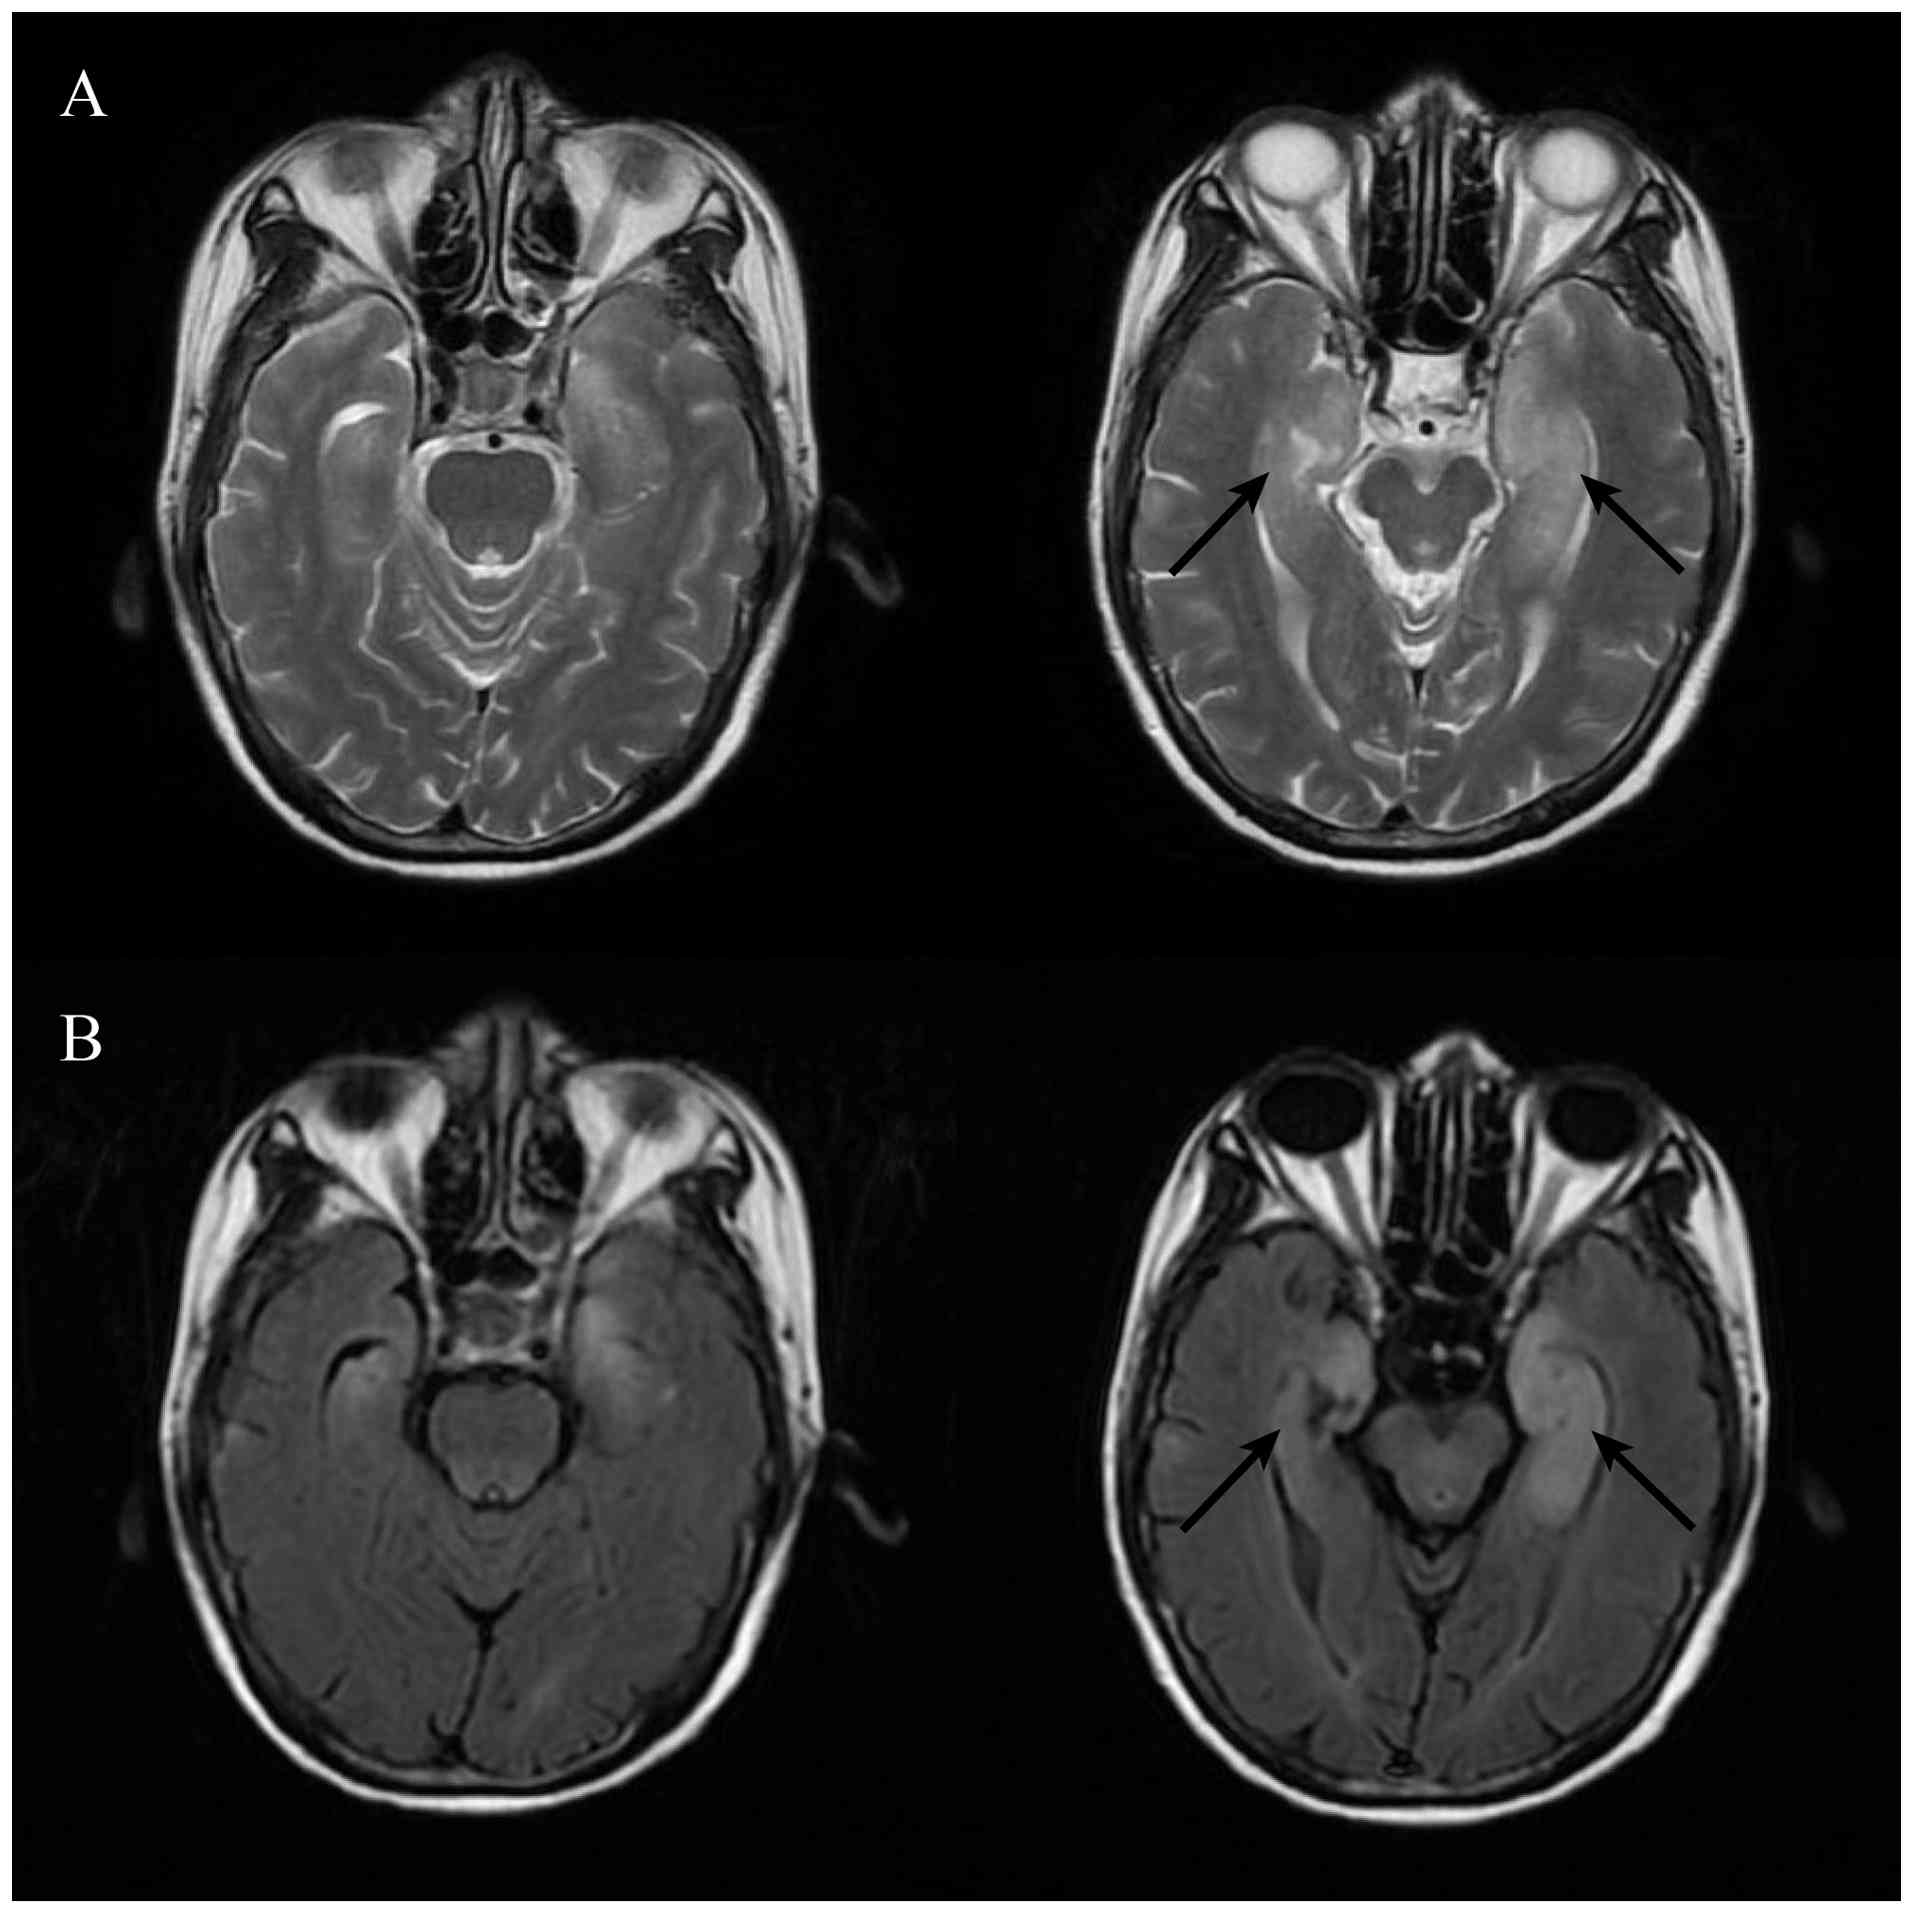

In June 2020, the patient was diagnosed with extensive-stage SCLC based on the results of biopsy of the left supraclavicular lymph node (hematoxylin and eosin staining and immunohistochemical staining performed using standard procedures; obtained from the pathology report; images are not available). Magnetic resonance imaging (MRI) before medical treatment showed no abnormal findings in the brain (Fig. 3). Subsequently, 2 days later, the patient was administered one 21-day cycle of chemotherapy with a combination of etoposide [100 mg/m2 intravenously (iv), days 1–3] and cisplatin (area under the curve 5 mg per ml/min iv, day 1). After three cycles of treatment, computed tomography depicted partial regression of the primary tumor and metastatic lymph nodes (Fig. 2B). In August 2020 (2 weeks after the second dose of atezolizumab), the patient developed self-reported confusion and short-term memory loss. Further physical examination revealed impairments in temporal and spatial orientation as well as poor calculation ability.

Magnetic resonance imaging before

medical treatment showed no abnormal findings in the brain on (A)

contrast-enhanced signal and (B) fluid-attenuated inversion

recovery signal.

Figure 3.

Magnetic resonance imaging before medical treatment showed no abnormal findings in the brain on (A) contrast-enhanced signal and (B) fluid-attenuated inversion recovery signal.